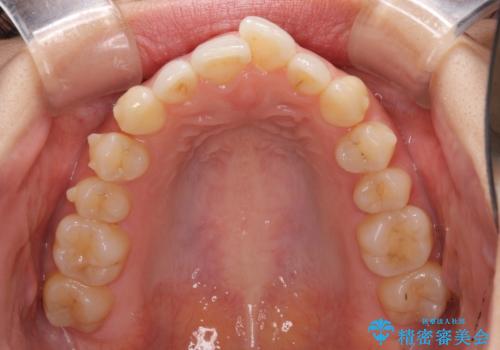

口が閉じにくい 1本飛び出した前歯の矯正治療

- 1本飛び出した前歯を治したいとのことで来院された患者様です。

歯列全体の拡大とIPR(歯と歯の間を削る)によってデコボコが解消するようにし、さらにゴムかけを活用して右側の咬み合わせ位置を変えるように設計し、インビザラインにより治療を行うこととしました。

後方移動に際し、上下顎の親知らずは3本とも抜歯することとしました。